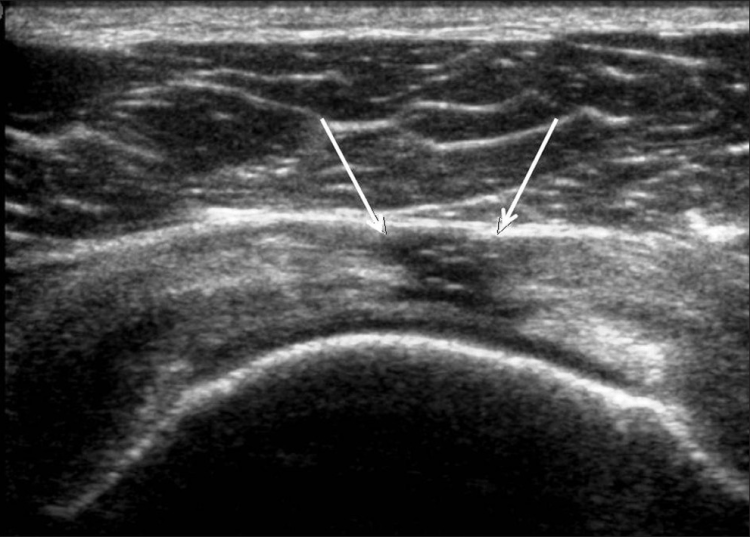

Los desgarros del manguito de los rotadores son la patología más común que se encuentra en los exámenes de ultrasonido del hombro.[7] La incidencia de lágrimas aumenta con la edad. Los desgarros de tendones se pueden clasificar de acuerdo con el grado de falla de la fibra, que van desde desgarros completos [Figura 7], desgarros de espesor total [Figuras 8, 9], desgarros de espesor parcial [Figuras 10-12] y desgarros intrasustancia [Figura 13 ]. Un desgarro agudo suele ir acompañado de derrame articular o bursal [Figura 12]. [7-9] La ausencia de derrame generalmente se relaciona con desgarros crónicos.[9] En un metanálisis sobre la precisión de la resonancia magnética, la artrografía por resonancia magnética y la ecografía en el diagnóstico de desgarros del manguito de los rotadores, la ecografía ofreció una alta sensibilidad y especificidad para la evaluación de los desgarros del manguito de los rotadores de espesor total (92,3 y 94,4 %, respectivamente) con 85,1 % y 92 %, respectivamente para todas las lágrimas.[7] El desgarro de espesor parcial aparece como un defecto o hendidura hipoecogénica en el tendón, afectando solo una parte de su espesor, mientras que un desgarro de espesor total se extiende desde la bolsa hasta la superficie articular del tendón. Un desgarro completo es un desgarro de espesor completo que afecta todo el ancho del tendón. El tendón se retrae medialmente, y la cantidad de retracción depende de la edad del desgarro. En las roturas crónicas, el tendón desaparece por debajo del arco coracoacromial, dejando la cabeza humeral descubierta por el supraespinoso, el denominado signo de la "cabeza desnuda". Los hallazgos de la ecografía incluyen la falta de visualización del tendón y la hernia del músculo deltoides. Los desgarros intrasustancia permanecen localizados en el tendón sin afectar sus márgenes. Los desgarros intrasustancia y de espesor parcial pueden ser difíciles de diferenciar de la tendinopatía focal.

Las patologías no relacionadas con desgarros del manguito rotador que se encuentran con más frecuencia son la tendinosis del manguito rotador [Figura 14], la tendinitis calcificante del manguito rotador [Figura 15] y el pinzamiento del tendón subacromial [Figura 16]. Vale la pena señalar que, en tales casos, se pueden desarrollar desgarros debido a la debilidad del tendón [Tabla 2].[79] La tendinosis o tendinopatía del manguito de los rotadores se presenta como inflamación del tendón con una ecotextura hipoecoica heterogénea del tendón. Las calcificaciones del manguito de los rotadores aparecen como focos hiperecogénicos, ya sea con una sombra posterior bien definida (Tipo I) o con una sombra tenue (Tipo II) o ausente (Tipo III). El Tipo I corresponde a la fase formativa y los Tipos II y III a la fase de reabsorción, en la que cambian a depósitos de calcio semi o totalmente líquidos. En el pinzamiento subacromial, el tendón no se desliza en el espacio subacromial durante la abducción y la elevación anterior del brazo.